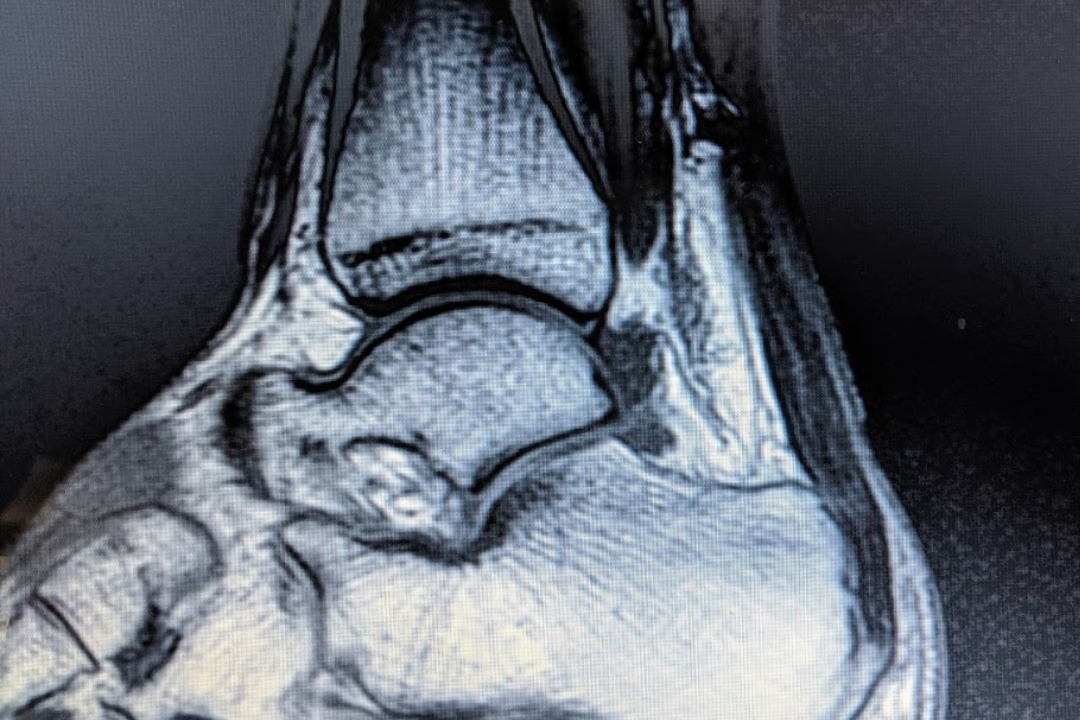

Recently Max suffered an Achilles tendon rupture and will have to undergo surgery. Please help us in raising as much as we can to help him pay for this costly procedure.